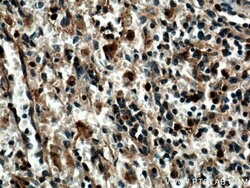

SYK Rabbit anti-Human, Mouse, Rat, Polyclonal, Proteintech

This gene encodes a member of the family of non-receptor type Tyr protein kinases. This protein is widely expressed in hematopoietic cells and is involved in coupling activated immunoreceptors to downstream signaling events that mediate diverse cellular responses, including proliferation, differentiation, and phagocytosis. It is thought to be a modulator of epithelial cell growth and a potential tumor suppressor in human breast carcinomas. Alternatively spliced transcript variants encoding different isoforms have been found for this gene.Specifications

| Immunohistochemistry (Paraffin) | |

| Human, Mouse, Rat | |